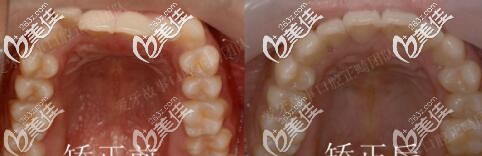

圖五下前牙對(duì)比

矯正用了1年半,地包天明顯改善,牙弓也擴(kuò)開(kāi)了。正畸期間口腔護(hù)理很重要,如果出現(xiàn)了口腔有異味或炎癥,就要隔兩到三天使用牙套清潔片把牙套泡一泡,必要時(shí)可用酒精棉片對(duì)牙套進(jìn)行消毒。